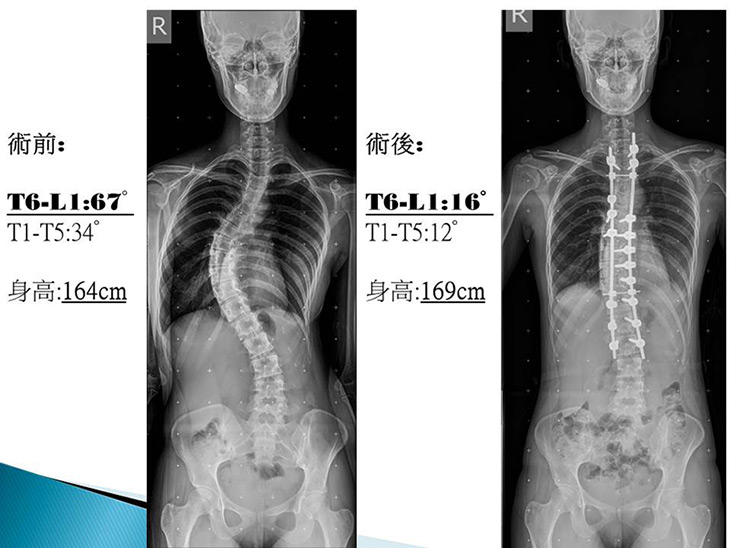

現年24歲的詹小姐國中時就發現有原發性脊椎側彎,但沒有固定追蹤,五年前至醫院就醫時,發現脊椎側彎已超過60度,胸腔和身形明顯扭曲不對稱,當時家人因擔心開刀矯正會造成癱瘓,所以一直沒接受手術。直到今年2月詹小姐因背痛不適就醫;經檢查發現側彎角度已經進展到67度,為了阻止側彎繼續惡化而影響心肺功能,詹小姐於6月接受了矯正手術,將原本的側彎67度矯正為16度,並且長高了5公分;詹小姐開心的感謝門諾醫療團隊,讓她更有自信面對未來的人生。